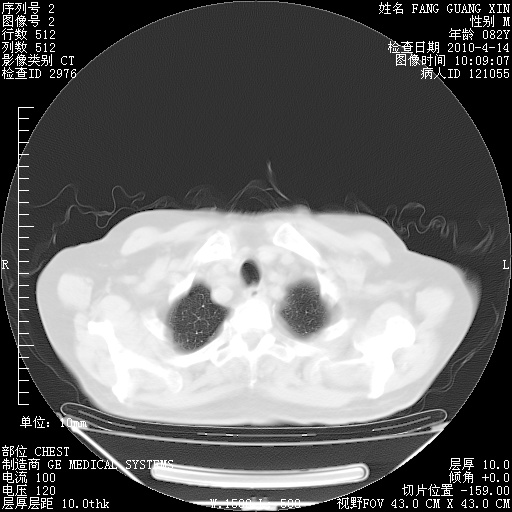

楼主| 发表于 2010-4-28 16:59 | 显示全部楼层

4月28日肺部CT——再次出现类似去年5月9日——透光度降低,(影像科认为)“间质性”改变。

1221483 1 .bmp

1221483 2 .bmp

1221483 3 .bmp

1221483 4 .bmp

1221483 5 .bmp